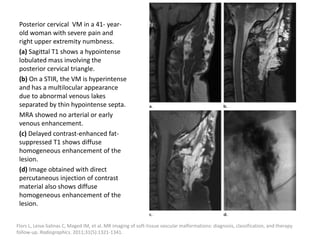

Posterior cervical VM in a 41- year-

old woman with severe pain and

right upper extremity numbness.

(a) Sagittal T1 shows a hypointense

lobulated mass involving the

posterior cervical triangle.

(b) On a STIR, the VM is hyperintense

and has a multilocular appearance

due to abnormal venous lakes

separated by thin hypointense septa.

MRA showed no arterial or early

venous enhancement.

(c) Delayed contrast-enhanced fat-

suppressed T1 shows diffuse

homogeneous enhancement of the

lesion.

(d) Image obtained with direct

percutaneous injection of contrast

material also shows diffuse

Flors L, Leiva-Salinas C, Maged IM, et al. MR imaging of soft-tissue vascular malformations: diagnosis, classification, and therapy

follow-up. Radiographics. 2011;31(5):1321-1341.